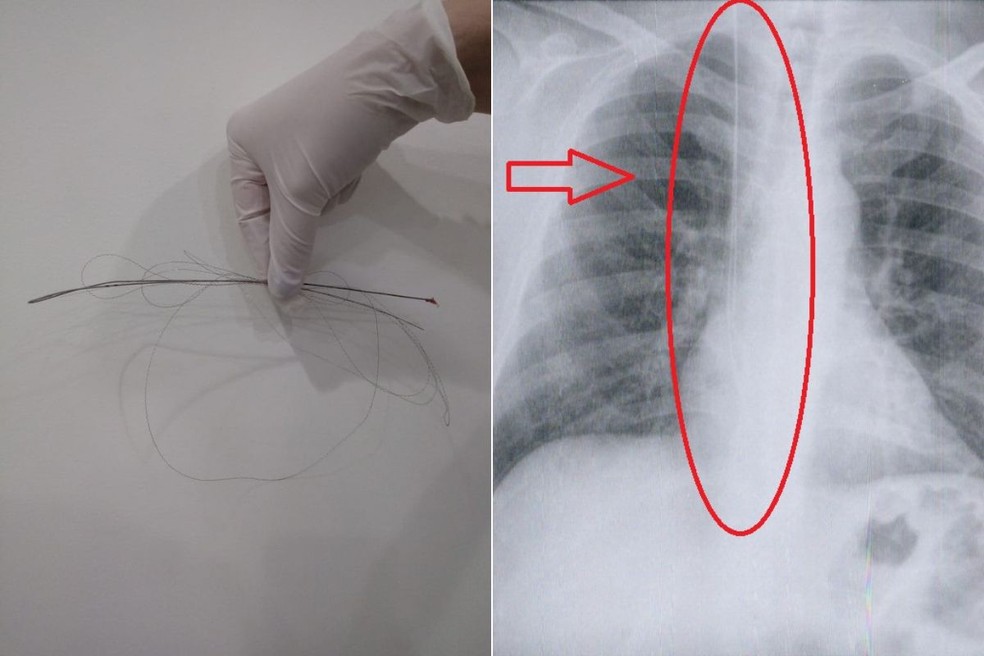

Em Campinas (SP), uma paciente viveu quatro anos com uma gaze que foi esquecida na barriga durante uma cesárea em um hospital particular. Já em Socorro (SP), uma jovem teve uma compressa que não foi retirada pelos médicos quando deu à luz de parto normal ao primeiro filho.

A dona de casa Cláudia Vicinança viveu quatro anos com uma gaze esquecida na barriga após uma cesárea em um hospital particular de Campinas. Ela sentia muitas dores, mas conta que só descobriu o problema quando resolveu ter um segundo filho.

As compressas feitas de gaze normalmente são usadas em grandes cirurgias para estancar sangramentos. Mas para que nada seja esquecido dentro do paciente, o Ministério da Saúde tem um protocolo que diz que todos os instrumentos e materiais devem ser contados antes e depois do procedimento.